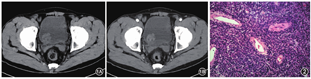

患者,男,70岁。因无痛性血尿3周于2019年5月24日入院。无尿频、尿痛,无腰酸、腰疼,无畏寒、发热。有多囊肾病史;吸烟史40年,20支/天。查体未见明显阳性体征。泌尿系超声检查示膀胱9点处占位,前列腺增生伴结石,双肾多发囊肿,部分囊壁钙化,双肾形态欠规则,皮质回声稍增强,右肾结石,双侧输尿管未见明显扩张。尿常规示潜血(++)。泌尿系CT平扫示膀胱三角区右侧占位,基底较宽,轮廓欠光整,呈分叶状,内部见低密度灶,最大长径约29 mm(图1A);增强扫描肿瘤不均匀强化,坏死区不强化(图1B),周围未见明显肿大淋巴结影。胸部增强CT未见异常结节影。诊断膀胱占位,恶性肿瘤可能。全麻下行经尿道膀胱肿瘤切除术(TURBT)。镜下见膀胱右后壁圆形新生物,大小约2.5 cm×2.5 cm,蒂宽,表面稍有充血水肿,前列腺Ⅱ度增生,双侧输尿管口未见喷血,余未见实质性占位。予电切环将肿块完整切除,并将肿块基底周围1 cm膀胱黏膜切除,深达肌层,术中将标本及周围组织分别送病理检查。

术后病理:送检组织大小为5.5 cm×4.5 cm×1.5 cm;镜下示梭形细胞密集排列,有异形,核分裂象最活跃处>10个/10HPF,局部见坏死(图2),肿块周围组织基底见肿瘤组织。免疫组化染色检查示S-100(+++)、GFAP(+++)、SOX-10(+++)、AE1/AE3(++)、PSA(-)、CK7(-)、CK20(-)、SMA(-)、Desmin(-)、GATA-3(-)、ALK(-)、HMB-45(-)、MyoD1(-)、EMA(-)、Melan-A(-)、CD57(-)、CK8/18(小灶+)、CD34(血管内皮细胞+)、CD31(血管内皮细胞+)、Ki-67(约20%+)。诊断为恶性外周神经鞘膜瘤(malignant peripheral nerve sheath tumors,MPNSTs)。术后第1天予吉西他滨膀胱灌注,术后第7天拔除导尿管出院。告知患者肿瘤高复发风险,患者仍要求保留膀胱,但因首次电切术后病理示肿块周围组织基底见肿瘤组织,术后1个月行二次电切术,病理未见肿瘤残留,术后未行辅助放化疗。第2次手术后门诊行吉西他滨膀胱灌注治疗,灌注方案:每周1次灌注8次,后每月1次灌注12次。第2次术后3、6、12个月复查膀胱镜未见复发,第2次术后9个月复查胸腹部CT及尿常规未见明显异常。